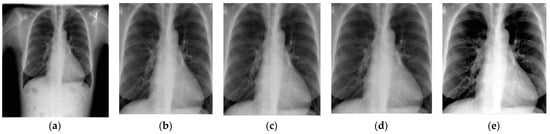

4.2.1. Image Preprocessing

4.2.1.1. Image Cropping

4.2.1.2. Noise Removal

4.2.1.3. Contrast Enhancement